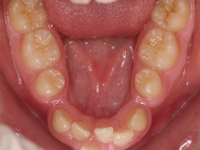

La paciente O.O. acude a nuestra consulta por:

– Canino 13 e incisivo lateral 42 en posición ectópica.

– Canino 23 incluido.

Con lo que decide realizarse un tratamiento de ortodoncia de duración de 24 meses con brackets damon Q.

CASO COMPLETO: